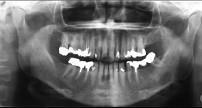

问题 黏液表皮样癌(如组图)以下哪种说法不正确 ( )

选项 A.低分化者常见颈淋巴转移 B.高分化者少见颈淋巴结转移 C.一般分为高分化和低分化两类 D.各型治疗原则相同 E.多发生在腮腺

答案 D